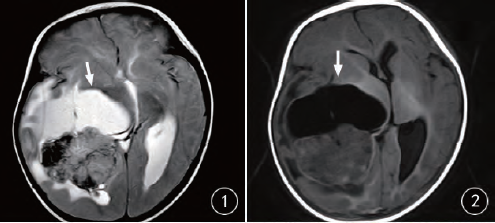

橫紋肌樣瘤是一種罕見的腫瘤,但生命綠洲卻憑借其獨特的醫(yī)療視角和先進的設(shè)備,走在治療的前沿,這里采用的治療技術(shù)不僅結(jié)合了傳統(tǒng)手術(shù)的優(yōu)勢,還融入了最新的生物技術(shù)、基因療法和免疫治療等前沿科技,經(jīng)驗豐富的醫(yī)療團隊緊跟國際醫(yī)學(xué)的最新進展,不斷嘗試將最新的研究成果應(yīng)用到臨床實踐中。